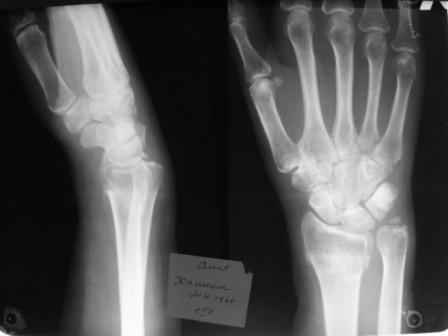

Уважаемые коллеги.Прошу обсудить случай лечения перелома дистального метаэпифиза лучевой кости. Ситуация скандальная и крайне неблагоприятная. Больная с патологической обстоятельностью мышления, склонностью к сутяжничеству, патологическими умозаключениями, не поддающимися коррекции (см. психиатрию, правда офиц. диагноза нет). В данном случае есть ряд ошибок с нашей стороны, прежде всего в отношении качества ведения документации (за что получил административное взыскание, по делом мне дураку). В остальном- придерживались в лечении подхода классический советской школы. Так как умную операцию…… сами знаете… 15.12- перелом луча в Москве. Там же репозиция, гипс. Дальнейшее лечение у нас в ЦРБ. 20.12.- вторичное смещение в гипсе21.12- под внутривенным наркозом- репозиция, гипсовая лонгета. Дальше начинается самое интересное. После репозиции больная заявила, что я (репозицию делал я) порвал ей все связки в суставе, посинел у нее 5 палец, якобы я за него тянул и т. д. На самом деле на 2 сутки после репозиции рука немного отекла и было незначительное сдавление гипсом, который был ослаблен. Дальнейшее лечение консервативное. Через 6 недель- гипс снят, назначено ЛФК. Пациентка крайне недовольна. Говорит, что на снимке у нее выступает кость, я ей сломал руку и.т.д. В общем началось. Пациентка прочитала в интернете наверное все, что есть по данной травме.По заключениями рентгенологов и консультанта из КДЦ областной больницы - стояние отломков допустимое. Объективно говоря- снижена высота лучевой кости, диастаз лучелоктевого сочленения, и не сросся шиловидный отросток. однако на РКТ при сравнении с другой стороной- разница незначительная. Дальше в одной из больниц нашей области и одной из больниц Москвы (вроде бы КГБ 53) врачи сказали, что репозиция сделана плохо. Нужна операция (восстановить длину лучевой кости), даже один из них предложил РЕДРЕССАЦИЮ (хи-хи) с наложением аппарата Илизарова. Что это для данной больной- радость неописанная. (см. описание психического статуса). Ничем другим, кроме зарабатывания дешевого авторитета объяснить данный факт не могу.Кстати, у больной еще нейропатия локтевого нерва.Для разрешения конфликта больная направлена на консультацию в ЦИТО на 03.03.11.

Теперь вопросы: 1.Прошу объективно оценить качество нашей репозиции на момент 21.12. (неужели так плохо?). Что на снимках при снятии гипса- сам вижу. 2. сравнить снимки РКТ (с двух сторон)- так ли велико укорочение лучевой кости и лучелоктевой диастаз. 3. Ваши мнения, в отношении целесообразности оперативного лечения учитывая ВСЕ вышеизложенное. 4. На всякий случай для суда- мог ли я тракцией в 2- 3 кг за 1 и 2 пальцы под внутривенным наркозом неправильно вколотить отломки и травмировать локтевой нерв. Кстати, в США если врач пациенту говорит, что его плохо лечили- то этого врача лишают лицензии. У нас наооборот- обгадить другого милое дело. И это процветает. От себя же могу сказать, что никто в нашем отделении так не поступает. Коллеги, будьте осторожны в своих высказываниях. От осложнений и ошибок никто не застрахован. А в данном случае многое будет зависеть от заключения консультантов поликлиники ЦИТО, куда больная направлена областным травматологом на 03.03 для решения вопроса о дальнейшей тактики лечения. С уважением ко всему травматологическому сообществу Дедок Михаил.

1. РЕПОЗИЦИЯ сделана качественно(ОСНОВНЫЕ 2 УГЛА ВЫСТАВЛЕНЫ ПРАВИЛЬНО ) , но перелом нестабильный и склонен к втор смещению . Поэтому мы стараемся все переломы со смещением фиксировать 3-МЯ спицами по GRIN методике .

1. Репозиция от 21.12.10 была выполнена лучше, чем первичная.